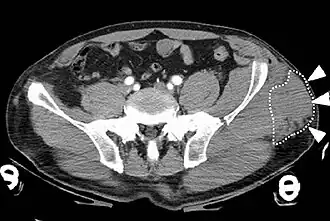

Syndrome de Morel-Lavallée au niveau du bassin gauche observée au scanner.

Le syndrome de Morel-Lavallée (SML) ou lésion de Morel-Lavallée (MLL) est un type de blessure[1] caractérisée par un épanchement de liquide sérolymphatique consécutif à un traumatisme qui survient de manière tangentielle[3] sur un tissu fortement vascularisé. Ce traumatisme provoque la désolidarisation des tissus cutanés et sous-cutanés par rapport aux couches musculaires et aux fascias situés en-dessous, sans rupture de la peau[4],[5]. À la suite de ce décollement cutané, se crée un espace dans lequel le liquide sérolymphatique s'accumule.

La lésion se situe généralement au niveau de la cuisse ou du bassin ; même si d'autres régions du corps peuvent être impliquées[1]. Les symptômes comprennent des ecchymoses, une mobilité cutanée accrue et un gonflement[1]. Cela peut ne pas apparaître avant quelques jours[1]. Les complications peuvent consister en une infection ou une anomalie de la zone concernée[1].

Les blessures associées peuvent inclure des fractures du bassin ou du fémur[1]. Le mécanisme sous-jacent implique la séparation du tissu sous-cutané du fascia situé en dessous, sans rupture de la peau[1], Cela crée un espace dans lequel le fluide s'accumule[2]. Le diagnostic se fait à partir d'un examen physique et peut être étayé par imagerie médicale[1].